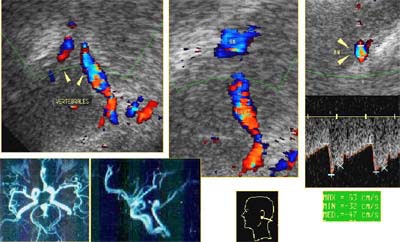

"Transcranial Doppler sonography is a new clinical and research application of ultrasound that allows a noninvasive examination to evaluate the brain circulation and cerebral perfusion, and measure blood-flow velocities in the cerebral vessels," Pérez said.

The system has multiple clinical applications in neurology, surgery, and stroke, as well as research, he said. The hospital uses a pulsed technique with 2-MHz pulse sound emission, very low frequency and high power, and a 7.5-MHz transducer with color-coded duplex Doppler. They use Combison 420 and Voluson 530D scanners manufactured by Kretz, Austria (now a GE Medical Systems company). Data can generally be obtained in the brain tissue anywhere between 25 mm and 100 mm from the transducer.

In neurology applications, the technique can be used to detect intracranial and extracranial stenosis, and to evaluate collateral circulation and vasomotor reactivity. It is routinely used for preoperative diagnoses of aneurysms and arteriovenous malformations, Pérez said, as well as in the detection of central nervous system tumors and brain necrosis by noting a lack of blood flow.

"Cerebrovascular diseases of the brain can be detected by increased or decreased blood flow, absence of the flow, and spectral changes," Pérez said. By comparing normal-velocity flows with measured flows, vessel patency can also be assessed. "Once you know the mean blood flow in a vessel, you have a very good idea of its physiology," he said.

Arteriovenous malformations are evaluated by identifying "nests" of malformed blood vessels. They are characterized by increased systolic and diastolic blood flow with decreased hemodynamic resistance, as well as increased velocity and turbulence in the ipsilateral extracranial carotid artery, according to Brague.

"In this patient we can see the entire 'nest' of malformation, and identify in this case a very dilated mid-cerebral artery with fast flow and high diastolic values throughout," she said.